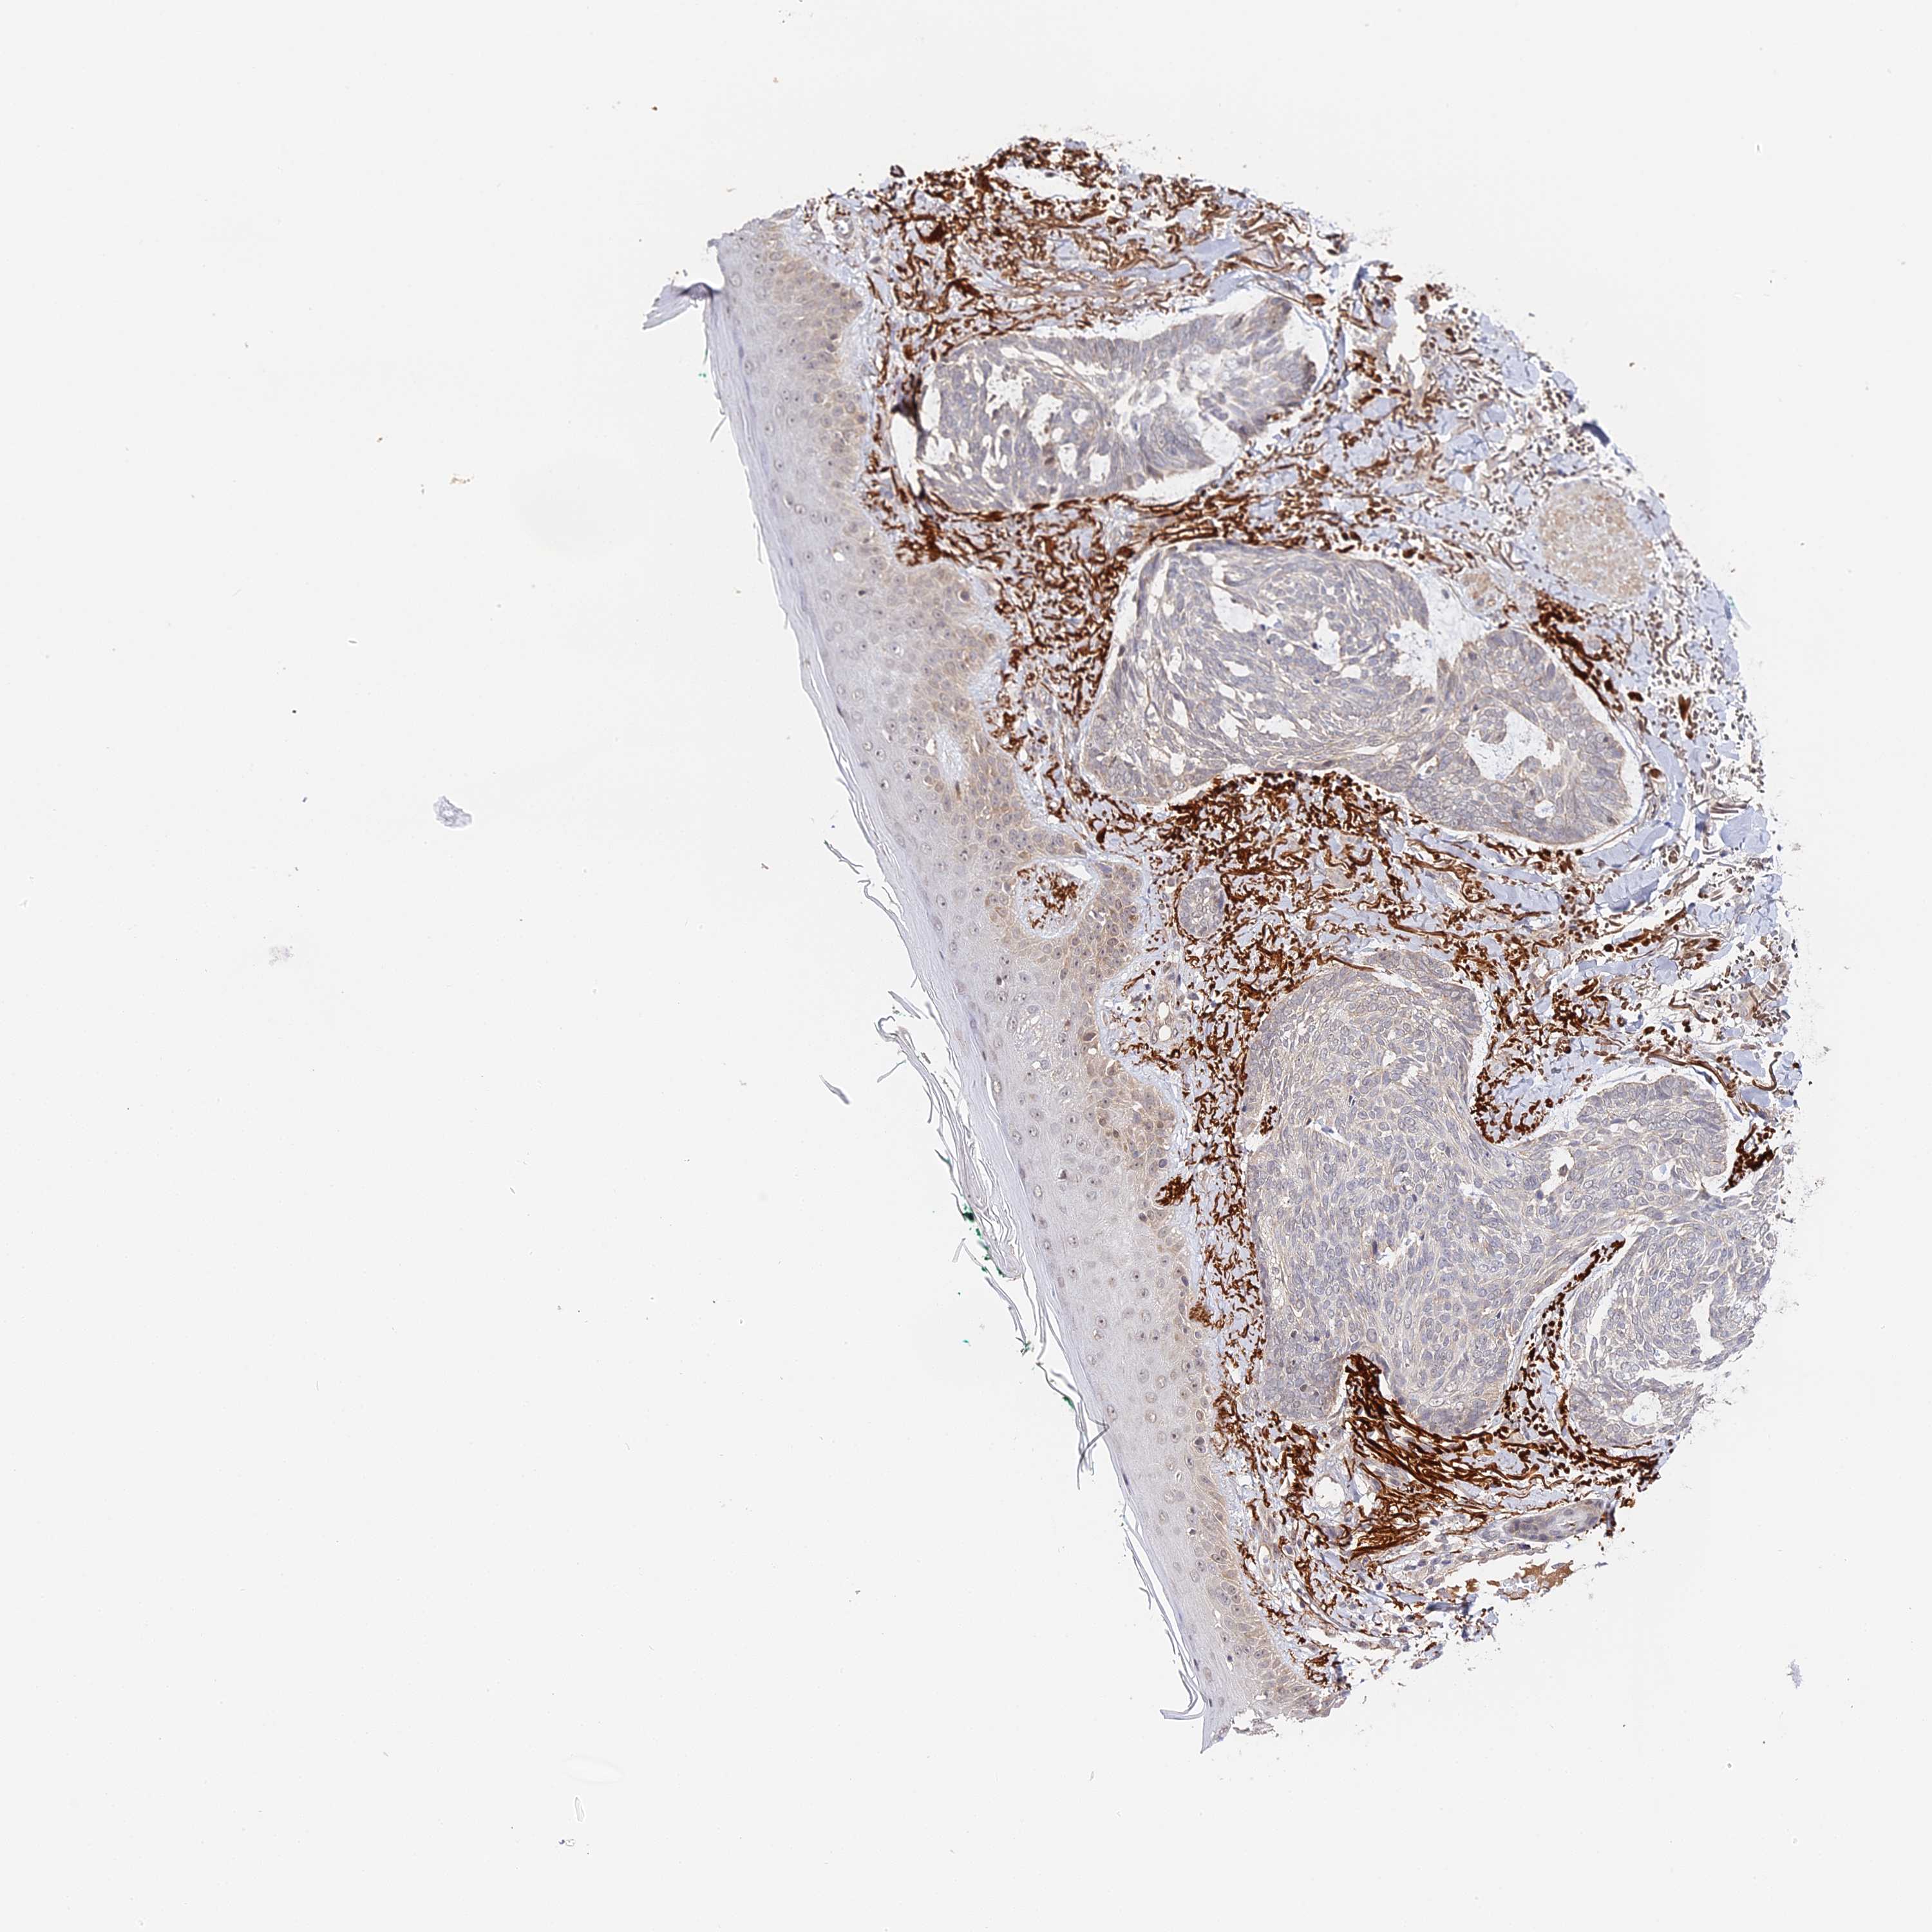

SKIN CANCER - Protein expressioni

A mouse-over function shows sample information and annotation data. Click on an image to view it in a full screen mode. Samples can be filtered based on level of antibody staining by selecting one or several of the following categories: high, medium, low and not detected. The assay and annotation is described here.

Antibody stainingi

Antibody staining in the annotated cell types in the current human tissue is reported as not detected, low, medium, or high, based on conventional immunohistochemistry profiling in selected tissues. This score is based on the combination of the staining intensity and fraction of stained cells.

Each image is clickable and will lead to virtual microscopy that enables deeper exploration of all samples and also displays staining intensity scores, fraction scores and subcellular localization as well as patient and tissue information for each sample.

Antibody HPA041045

Antibody HPA041968

Squamous cell carcinoma, NOS

Basal cell carcinoma